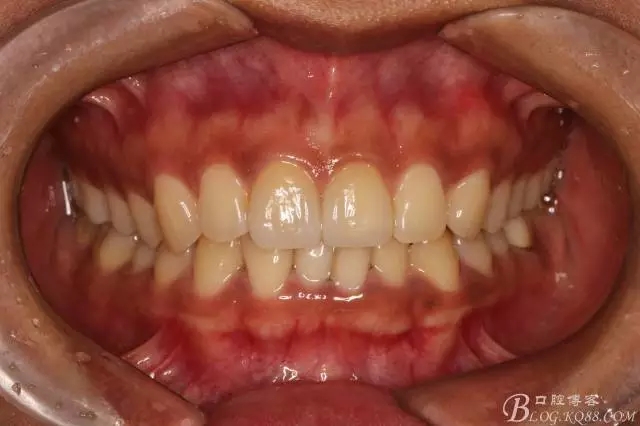

半年后(2016.9)復(fù)查照(這次復(fù)查已完全適應(yīng)修復(fù)后的效果,冷熱也不敏感了,我的心也就放下了)